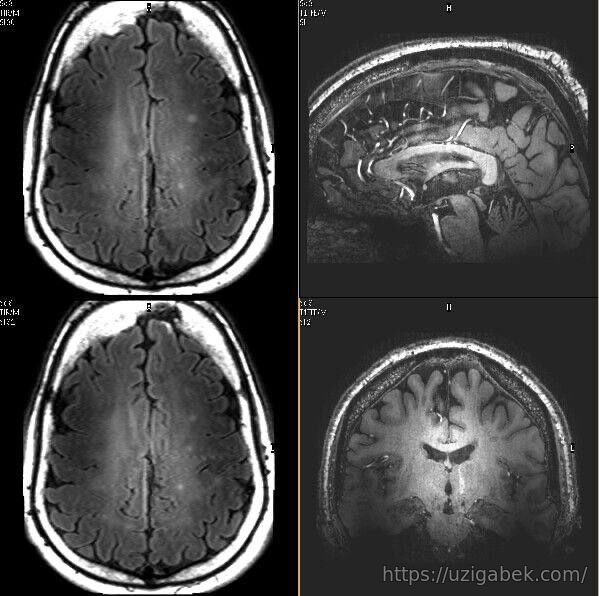

| Biz o'zimiz haqimizda qanchalik kam ma'lumotga egamiz. Miyada qanday reaktsiyalar sodir bo'ladi va unga qanday qilib to'g'ri ta'sir qilish kerak-bularning barchasi asosan sirdir.

Maxsus tadqiqotlar o'tkazildi, unda tomografga joylashtirilgan odamga oddiy mantiqiy vazifalar berildi. Ushbu tadqiqotlar natijalari shunchalik hayratlanarli ediki, dastlab olimlarning o'zlari ularga ishonishdan bosh tortdilar.

Gap shundaki, tomograf tomonidan qayd etilgan faoliyatga ko'ra, miya qaror qabul qilgan paytdan boshlab, odam javob bergan paytgacha bir necha soniya o'tdi.

Nerv impulslarining tarqalish tezligi uchun bu juda ko'p, ya'ni uni oddiy kechikishlar bilan bog'lash mumkin emas edi. Ma'lum bo'lishicha, biz biron bir vazifaga javob berishdan bir necha soniya oldin, miya mustaqil ravishda qanday javob berish to'g'risida qaror qabul qilgan.

Ammo bundan ham hayratlanarlisi, shundan keyin miya odamga o'ziga xos turtki yubordi: "xavotir olmang, siz faqat o'zingiz qaror qildingiz".